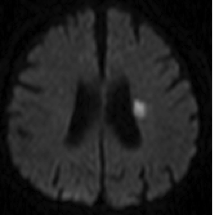

1)ラクナ梗塞

脳の中の細い血管が1本詰まることにより起きる脳梗塞です。脳が壊死する範囲は比較的狭く、軽症で済むことが多く、命に関わることはありません。しかし詰まる場所によっては重い半身麻痺などの後遺症が残ることもあります。治療は点滴と飲み薬が主体で手術が行われることはありません。この脳梗塞になる方はたいてい、高血圧症をもっています。